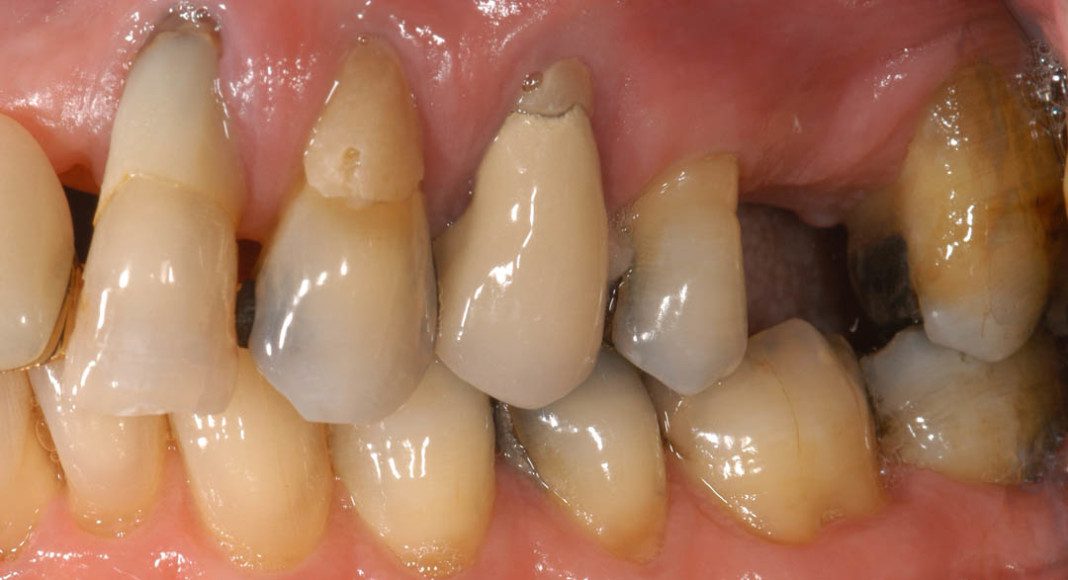

Pre-treatment, lips retracted. Notice the exposed roots on several of the back teeth, and the metal margins around some of the crowns? Also, she did not like the gum line above her two front teeth being uneven.

Pre-treatment, left lateral view. Notice the exposed margins of the old crowns from all the gum recession? These areas were very sensitive when she ate cold or sweet things. (We were able to correct that with the new crowns).